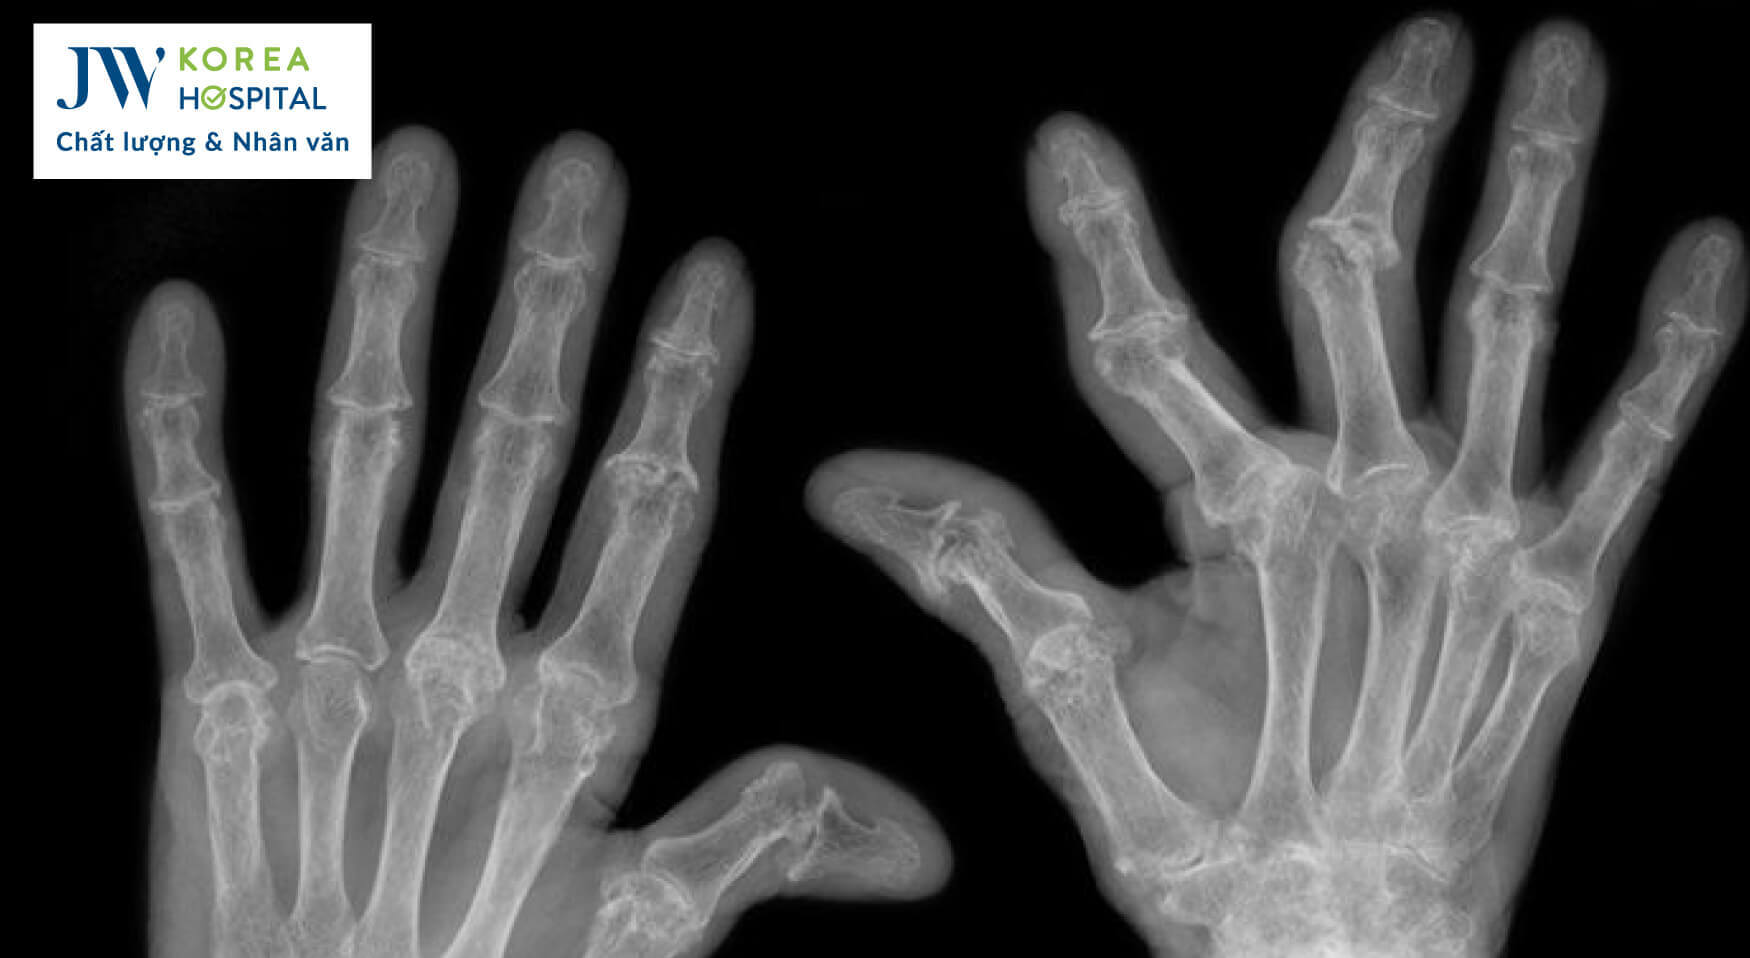

2. Viêm khớp dạng thấp

- Nguyên nhân: Rối loạn hệ miễn dịch khiến cơ thể tấn công các mô khớp

- Triệu chứng: Sưng, nóng, đỏ, đau khớp kéo dài, có thể kèm theo mệt mỏi, sốt

- Đối tượng: Phổ biến ở phụ nữ trung niên